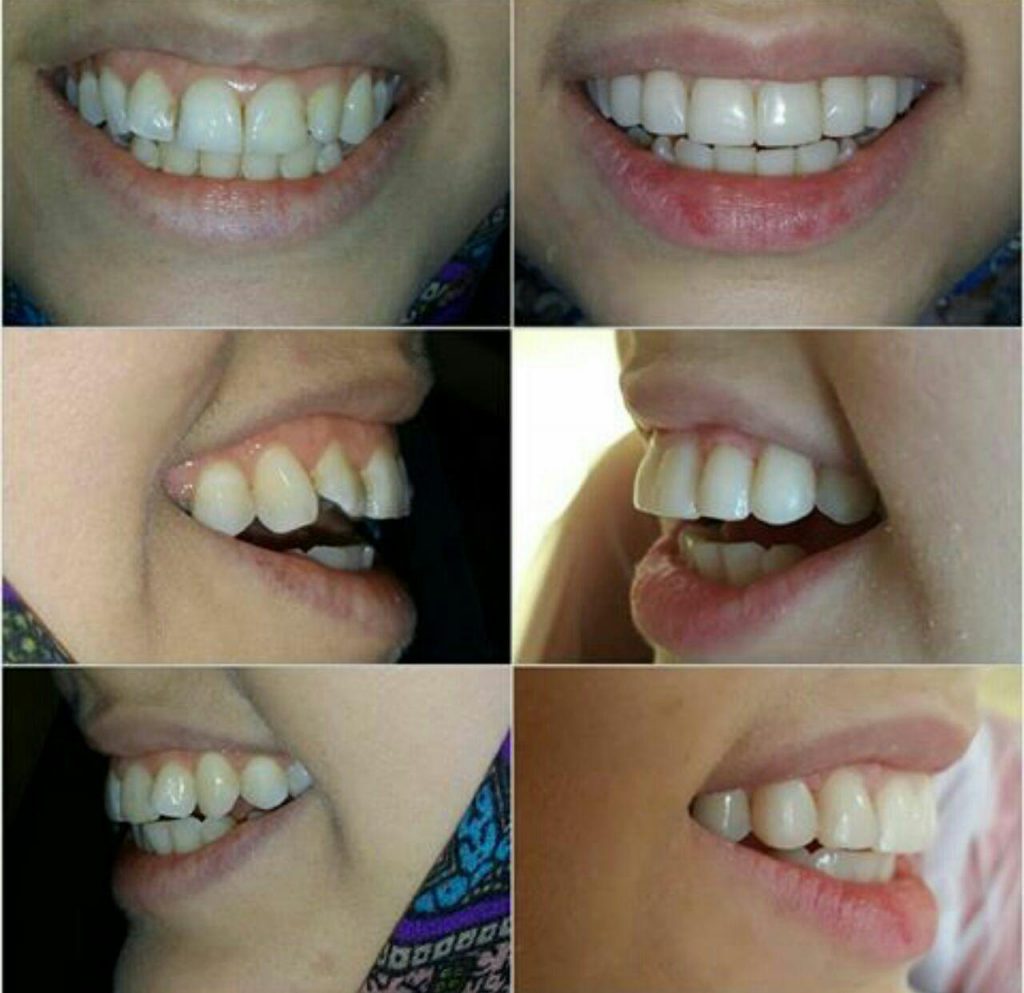

جراحی لثه _ لمینیت _ کامپوزیت ونیر

اصلاح طرح لبخند _ جرم گیری و بلیچینگ (سفید کردن دندان ها )

لبخند زیبارا به شما هدیه میدهیم